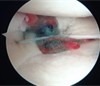

半月板は膝の内側と外側の両方に存在してクッションの役目を果たしており、外傷やスポーツなどによるオーバーユースにより損傷することがあります。また加齢による変性でも損傷します。手術では関節鏡を膝関節内に挿入して半月板の様子を確認してどのような手術を行うかを判断します。当院ではなるべく半月板を温存することを心掛けており、半月板縫合を行うことが多いですが、修復が難しい部位では部分切除が余儀なくされることもあります。

鏡視下膝半月板形成術

修復後(フィブリン+人工靭帯使用)